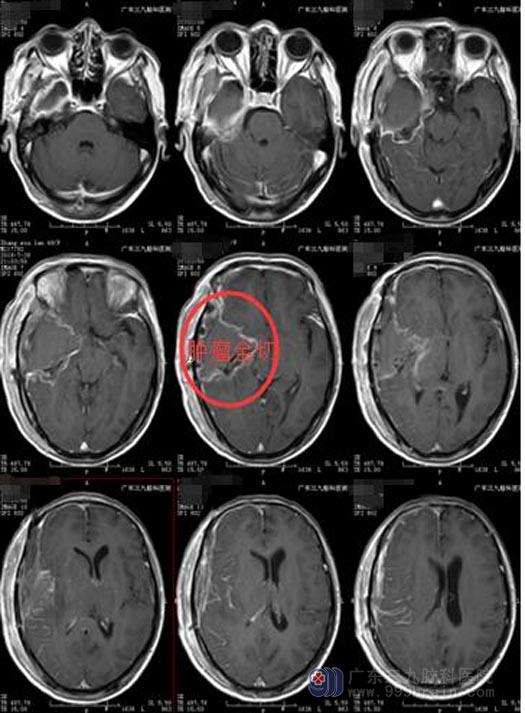

张女士及家属同意在“全麻下右侧颞岛叶占位性病变切除术”,手术顺利,术中仅出血200ml,病理诊断:右侧颞岛叶胶质母细胞瘤,IDH突变型,WHO IV级。

术后,张女士头痛症状缓解,生命体征平稳,意识清楚,病情稳定,等待进一步的放化疗。

手术后